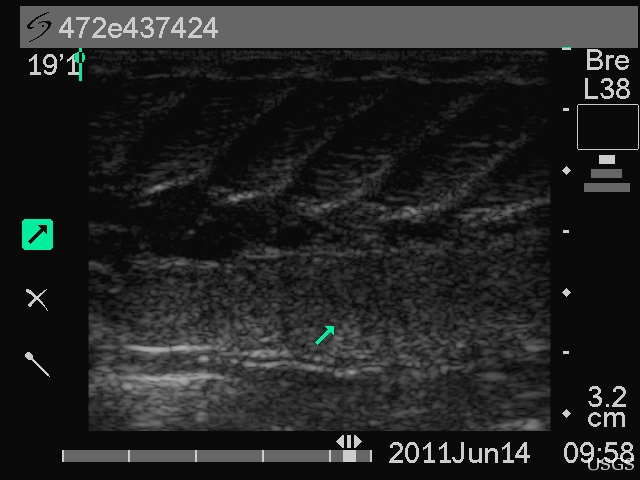

Post Ultrasound

The green arrow points to the ovary in this side view of the abdominal cavity of a telemetered pallid sturgeon.  An ultrasound image two months prior revealed mature oocytes (eggs) in this female.